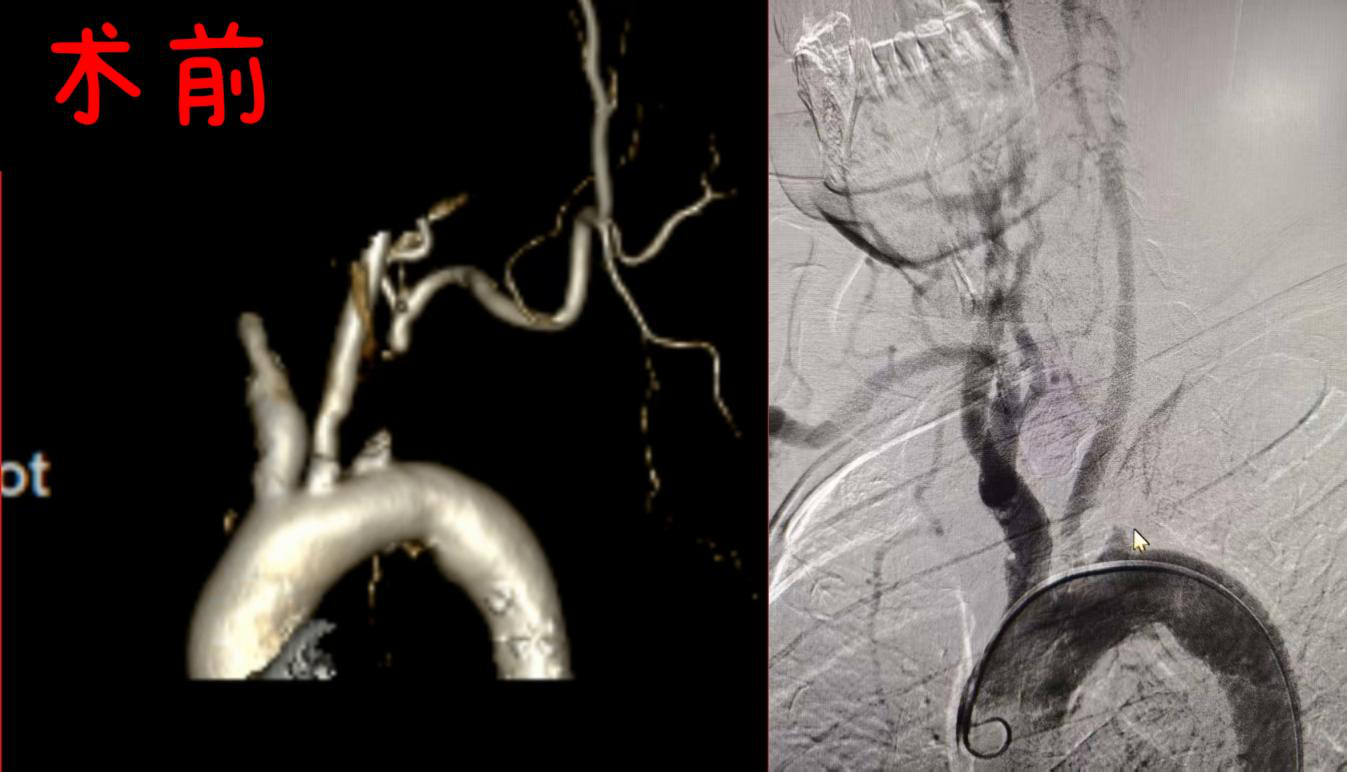

针对许大爷的病情,介入医学科团队为许大爷定制了最优方案-——“药涂球囊扩张+支架植入”。先用球囊扩张狭窄部位,再植入一枚药物涂层支架,将血管持久撑开,恢复正向血流;术中,医生仅通过其右侧大腿股动脉的一个穿刺小孔,送入细如发丝的导管与导丝,在血管造影的精准引导下,抵达闭塞的左锁骨下动脉;术后造影显示,原狭窄段血流通畅,左上肢血流立即改善。